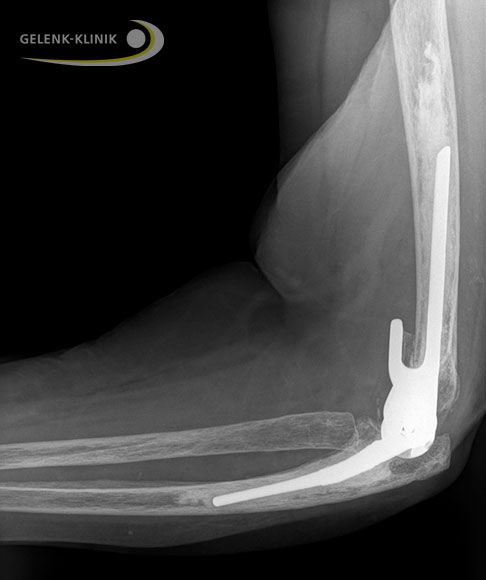

Seitliche Röntgenaufnahme einer gekoppelten Ellenbogenprothese mit Verankerung in Oberarm (Humerus) und Elle (Ulna). Das Radiusköpfchen wurde in diesem Fall gekürzt, um ein mechanisches Anstoßen an das Kunstgelenk zu vermeiden. Der gekoppelte Mechanismus stabilisiert die Ellenbogenprothese gegenüber Seitbewegungen. © Gelenk-Klinik

- Im Falle einer gekoppelten Prothese verbindet der Ellenbogenspezialist anschließend beide Prothesenteile von Ulna und Humerus miteinander.

- Beim Einsatz einer gekoppelten Ellenbogenprothese kürzt der Spezialist gegebenenfalls das Radiusköpfchen, um ein mechanisches Anstoßen des Knochens an die Prothese zu vermeiden. Die Stabilität des Ellenbogengelenkes bleibt auch dann durch den Kopplungsmechanismus der Prothese erhalten.